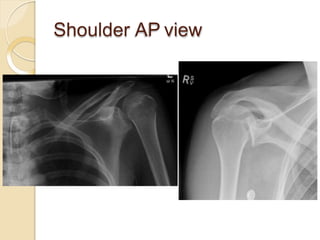

Shoulder AP view

Scapular Y-view